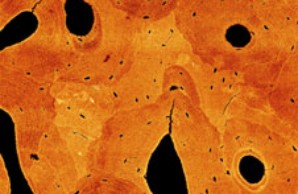

Bioengineering / Medical Technology

Pathological alterations in the structural integrity and elemental composition of the bone matrix impact fracture resistance significantly and thereby affect the patients health status. The aim of the Heisenberg Research Group is to decipher the underlying mechanisms at each level of bone’s complex hierarchical structure using a multiscale, integrated approach combining osseous cell imaging with bone quality assessment and medical imaging techniques.